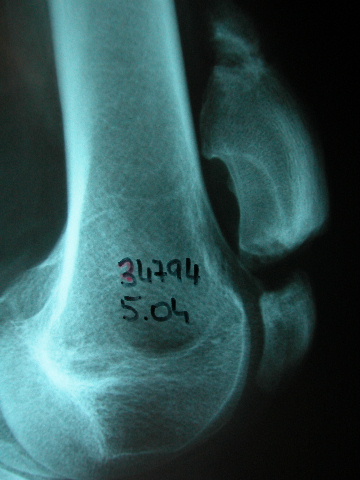

ACT artrosis muy severa de codo.